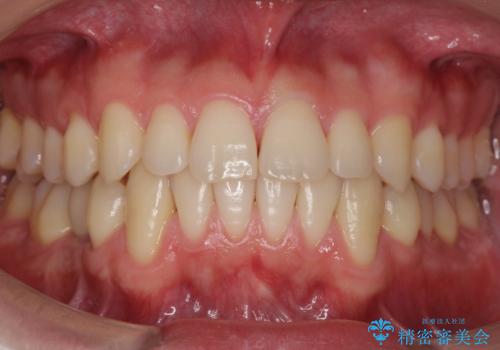

- 前歯の並びをきにして来院。

歯を抜かずに、やすりがけすることでスペースを獲得し、前歯をしっかり下げました。

また、インビザラインに先駆けて、右下はワイヤーによる部分矯正を行い、犬歯をしっかり後ろに下げました。

下げる時に、矯正用ミニスクリューを使用しています。

乳歯も根が吸収しており長くは持たない状況でしたので、まず乳歯を抜歯し、他の歯を矯正治療で歯を並べてからインプラントで補綴しました。

矯正治療→インプラントの順で行います。